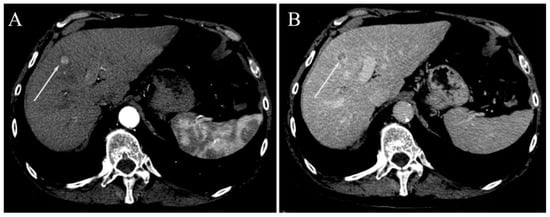

| Irregular margins | 21 (58.3%) | 26 (47.3%) | 0.391 |

| TTPVI | 14 (38.9%) | 11 (20%) | 0.058 |

| Peritumoral enhancement | 4 (11.1%) | 6 (10.9%) | 1.000 |